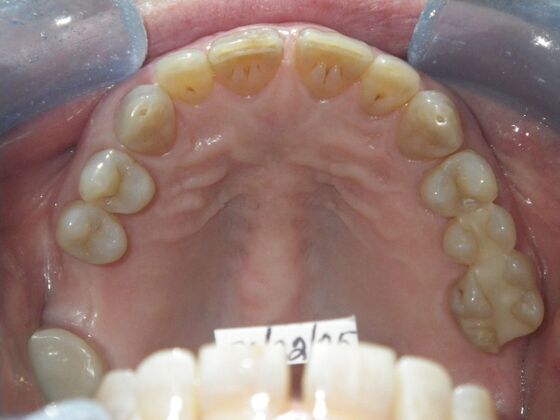

Cosmetic Changes with Veneers and Crown and Bridge: Case 1

Patient presented with spacing between upper central incisors and dark tetracycline stains that she wanted corrected